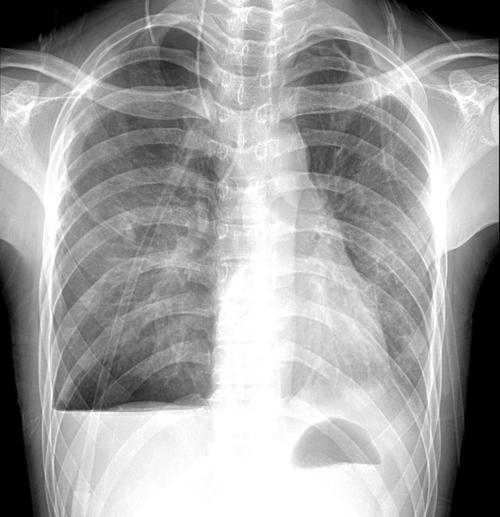

胸片做完多久可以怀孕